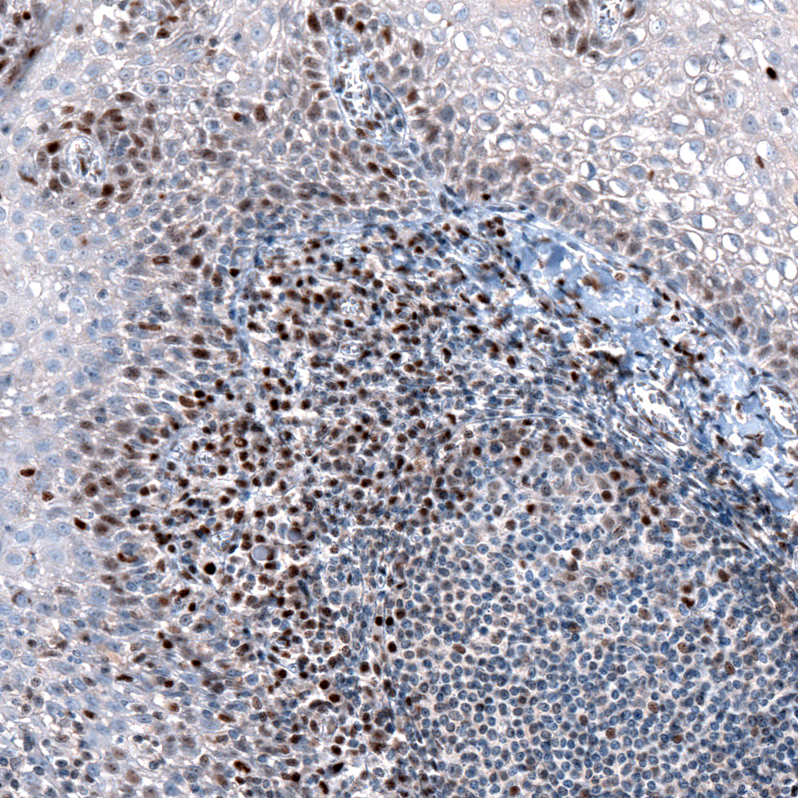

Immunohistochemistry analysis in human fallopian tube and skeletal muscle tissues using HPA023030 antibody. Corresponding SLFN11 RNA-seq data are presented for the same tissues.